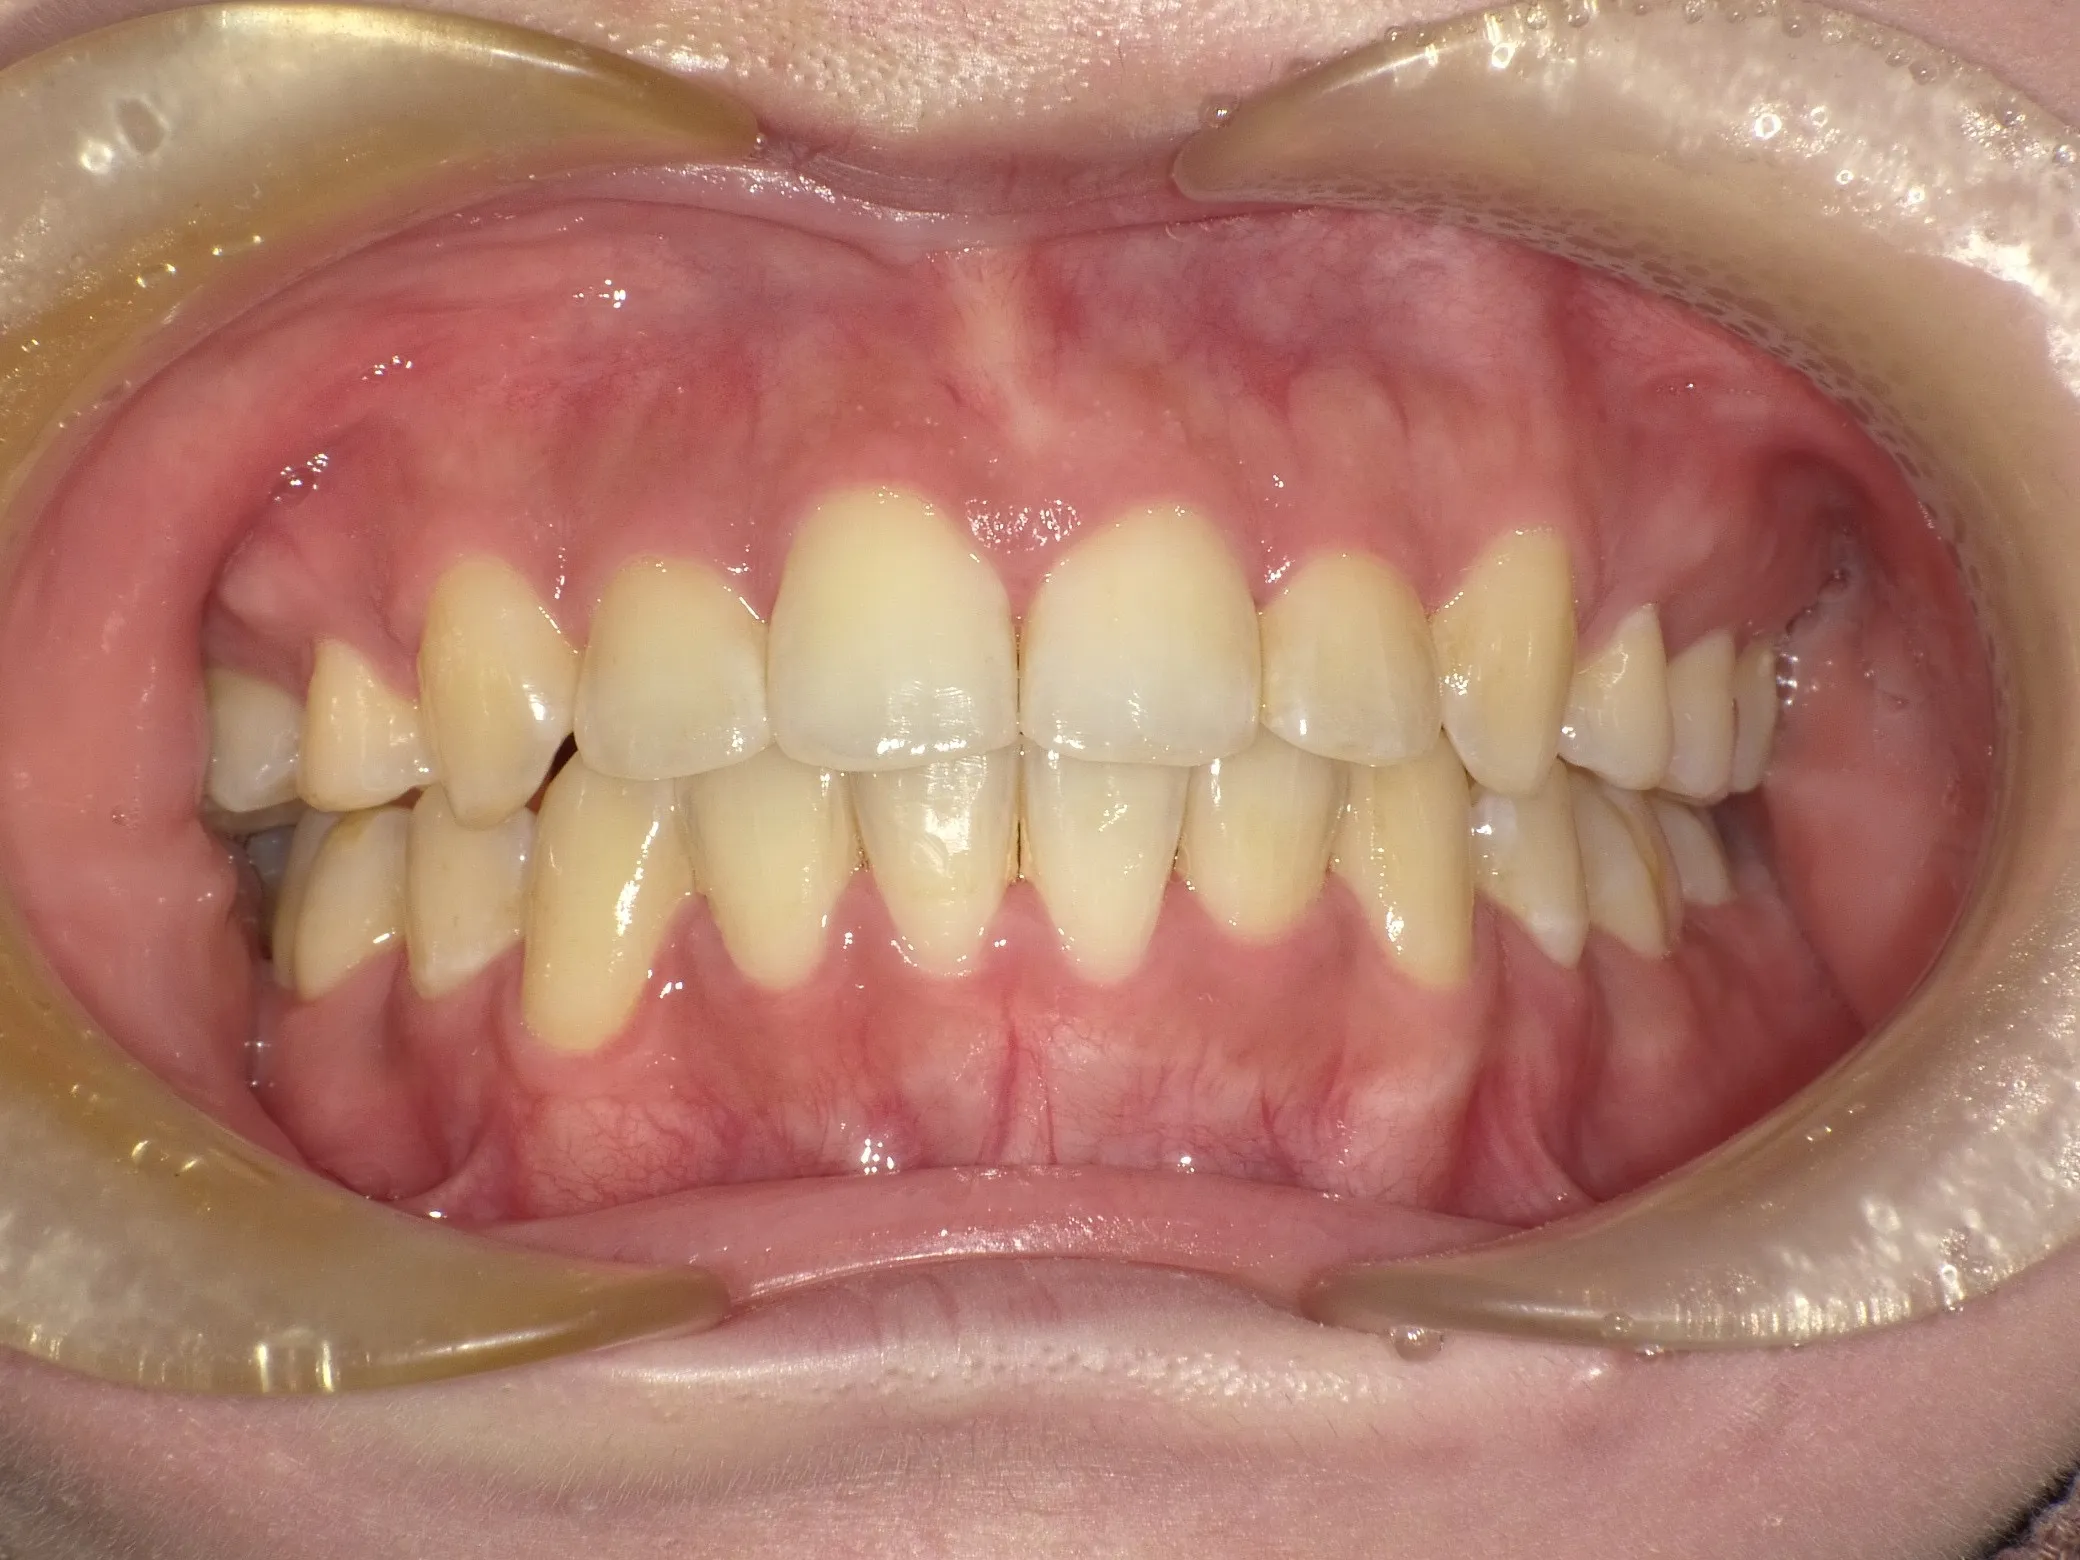

症例②

症例2_治療前 症例2_治療後

年齢・性別 31才・男性

治療方法 ブラケット矯正

治療期間 3年

治療総額 850,000円

特記事項 抜歯あり(4本抜歯)